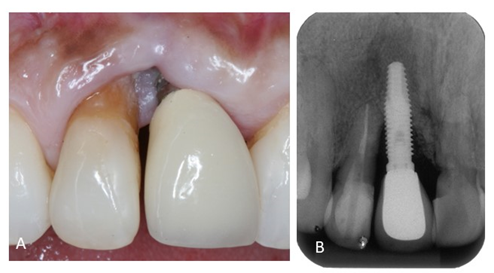

Durante exame clínico foi observada migração apical da margem gengival nos dentes 11 e 12 e acúmulo de biofilme na região. Radiograficamente notou-se que o dente 11 era um implante com perda óssea de aproximadamente metade do comprimento.

Após realização do periograma, paciente tinha 27% de sangramento a sondagem e 30% de índice de placa. Na região do implante 11 apresentou profundidade de sondagem igual a 6mm e recessão gengival de 4mm. E suspeita de reabsorção do dente 21. A paciente foi diagnosticada com doença periodontal crônica (P4) e peri-implantite.